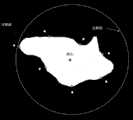

FIG. 3 is a schematic illustration of electrocoagulation location marking provided in an embodiment of the present application;

the geometric centroid of the abnormal region is determined by a connected domain method. As shown in fig. 3, one of the marked points in the white area is the centroid.

in some embodiments of the present application, the determining an injection point for endoscopic submucosal dissection of the abnormal region based on the geometric centroid of the abnormal region, the target boundary point and the preset electrocoagulation prompting region, as shown in the injection point at the upper left corner of fig. 3, may specifically be performed by using an intersection point of a ray and a boundary of the electrocoagulation prompting region far away from the geometric centroid as the injection point for endoscopic submucosal dissection of the abnormal region, wherein the ray is a ray connected with the target boundary point by the geometric centroid.

In some embodiments of the present application, as shown in fig. 4, the electrocoagulation marker comprises at least two electrocoagulation marker spots, and the determining of the electrocoagulation marker circumcircle based on the geometric centroid and the electrocoagulation marker comprises steps C1 and C2:

And C2, taking a circumscribed circle which is made by taking the distance between the target electrocoagulation mark point and the geometric centroid as a radius and the geometric centroid as a circle center as an electrocoagulation mark circumscribed circle.

Wherein the electrocoagulation marker circumcircles as in figure 4, the circumcircle before injection.